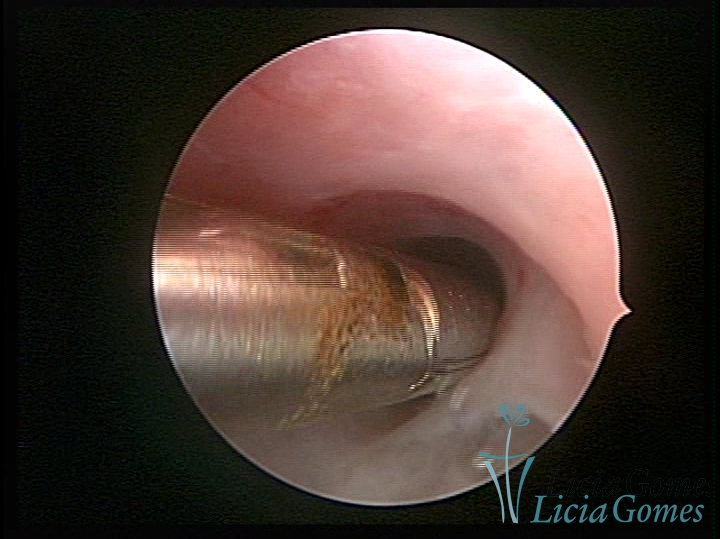

Sinéquia TIPO FIBROSA

As Sinéquia uterinas são cicatrizes (aderências) entre as superfícies das paredes uterinas, que podem ocorrer após manipulação cirúrgica, ou curetagem uterina, ou após um processo inflamatório na cavidade uterina (endometrite), podendo levar a alterações menstruais, infertilidade, e complicações obstétricas, como abortamento, parto prematuro.